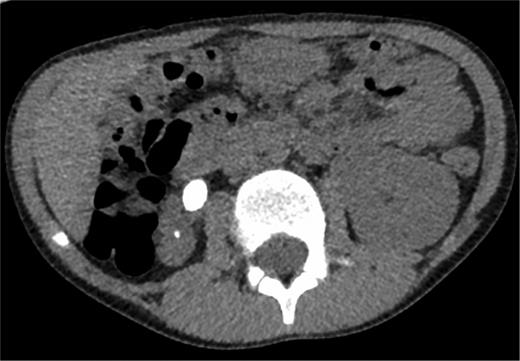

A 7-year-old boy who had no relevant past medical history (UTIs or other) presented with acute urinary retention. He was systemically well but had mild suprapubic discomfort and a palpable bladder. Examination of the penile shaft revealed a palpable hard swelling. The urethral meatus was patent. Following failure of conservative management of urinary retention (placing the boy in a warm-bath, adequate analgesia), a cysto-urethroscopy was performed under general anaesthetic. Due to lack of paediatric instruments on site, a 6.6-Fr adult ureteroscope was used. This revealed an obstructing urethral calculus impacted in the navicular fossa. The stone was fragmented using a HoYag laser and extracted. Cystoscopy with the same instrument then revealed multiple bladder calculi with a patulous right ureteric orifice. These stones were washed out and the patient was catheterized (6-Fr urethral catheter). Serum calcium, urate and renal function were normal. Post-operative ultrasound revealed a small, scarred right kidney and large (hypertrophied) left kidney. Micturating cystourethrogram demonstrated grade 1 and 2 VUR in the right and left ureters, respectively, and an opacification in the upper right ureter suspicious of a calculus. CT KUB confirmed a 4 cm (cranio-caudal) by 0.8cm (transverse) right ureteric calculus (Fig. 1). DMSA scan revealed 4% (right) split renal function. The patient subsequently underwent a right laparoscopic nephroureterectomy (Fig. 2).

Non-contrast CT demonstrating the large right ureteric calculus.